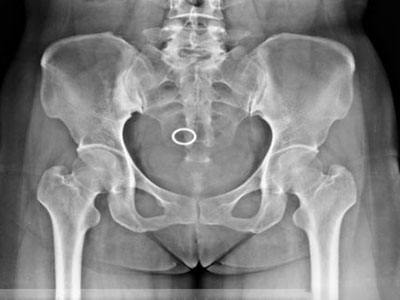

臨床表現(xiàn):癥狀多輕微,局部可有輕壓痛或肌肉痙攣。X線和CT上,髂骨耳狀面下均勻性高密度硬化,骨結(jié)構(gòu)不清,骨小梁間隙消失,內(nèi)緣以骶髂關(guān)節(jié)。骨質(zhì)硬化區(qū)表現(xiàn)為三角形、新月形或梨形,尖端向上,寬基向下。病變范圍不一,可累及耳狀面的全部或中下2/3,亦可僅限于中1/3或下1/3。椎體也可發(fā)病,多位于腰椎前上角,以L4、L5多見,多單發(fā),亦可累及多個椎體,表現(xiàn)位椎體前上緣三角形致密影,椎間縫正常。部分病例經(jīng)隨訪觀察病變范圍可縮小,骨硬化密度減低,但多數(shù)無任何改變。

常見的致密性骨炎:骶髂關(guān)節(jié)致密性骨炎

骶髂關(guān)節(jié)致密性骨炎臨床癥狀是患有復(fù)發(fā)性腰痛,有時可向下放射至臀部和大腿,但不是根性疼痛,腰活動時可加重癥狀,與妊娠、勞損及病灶性炎癥有關(guān)。